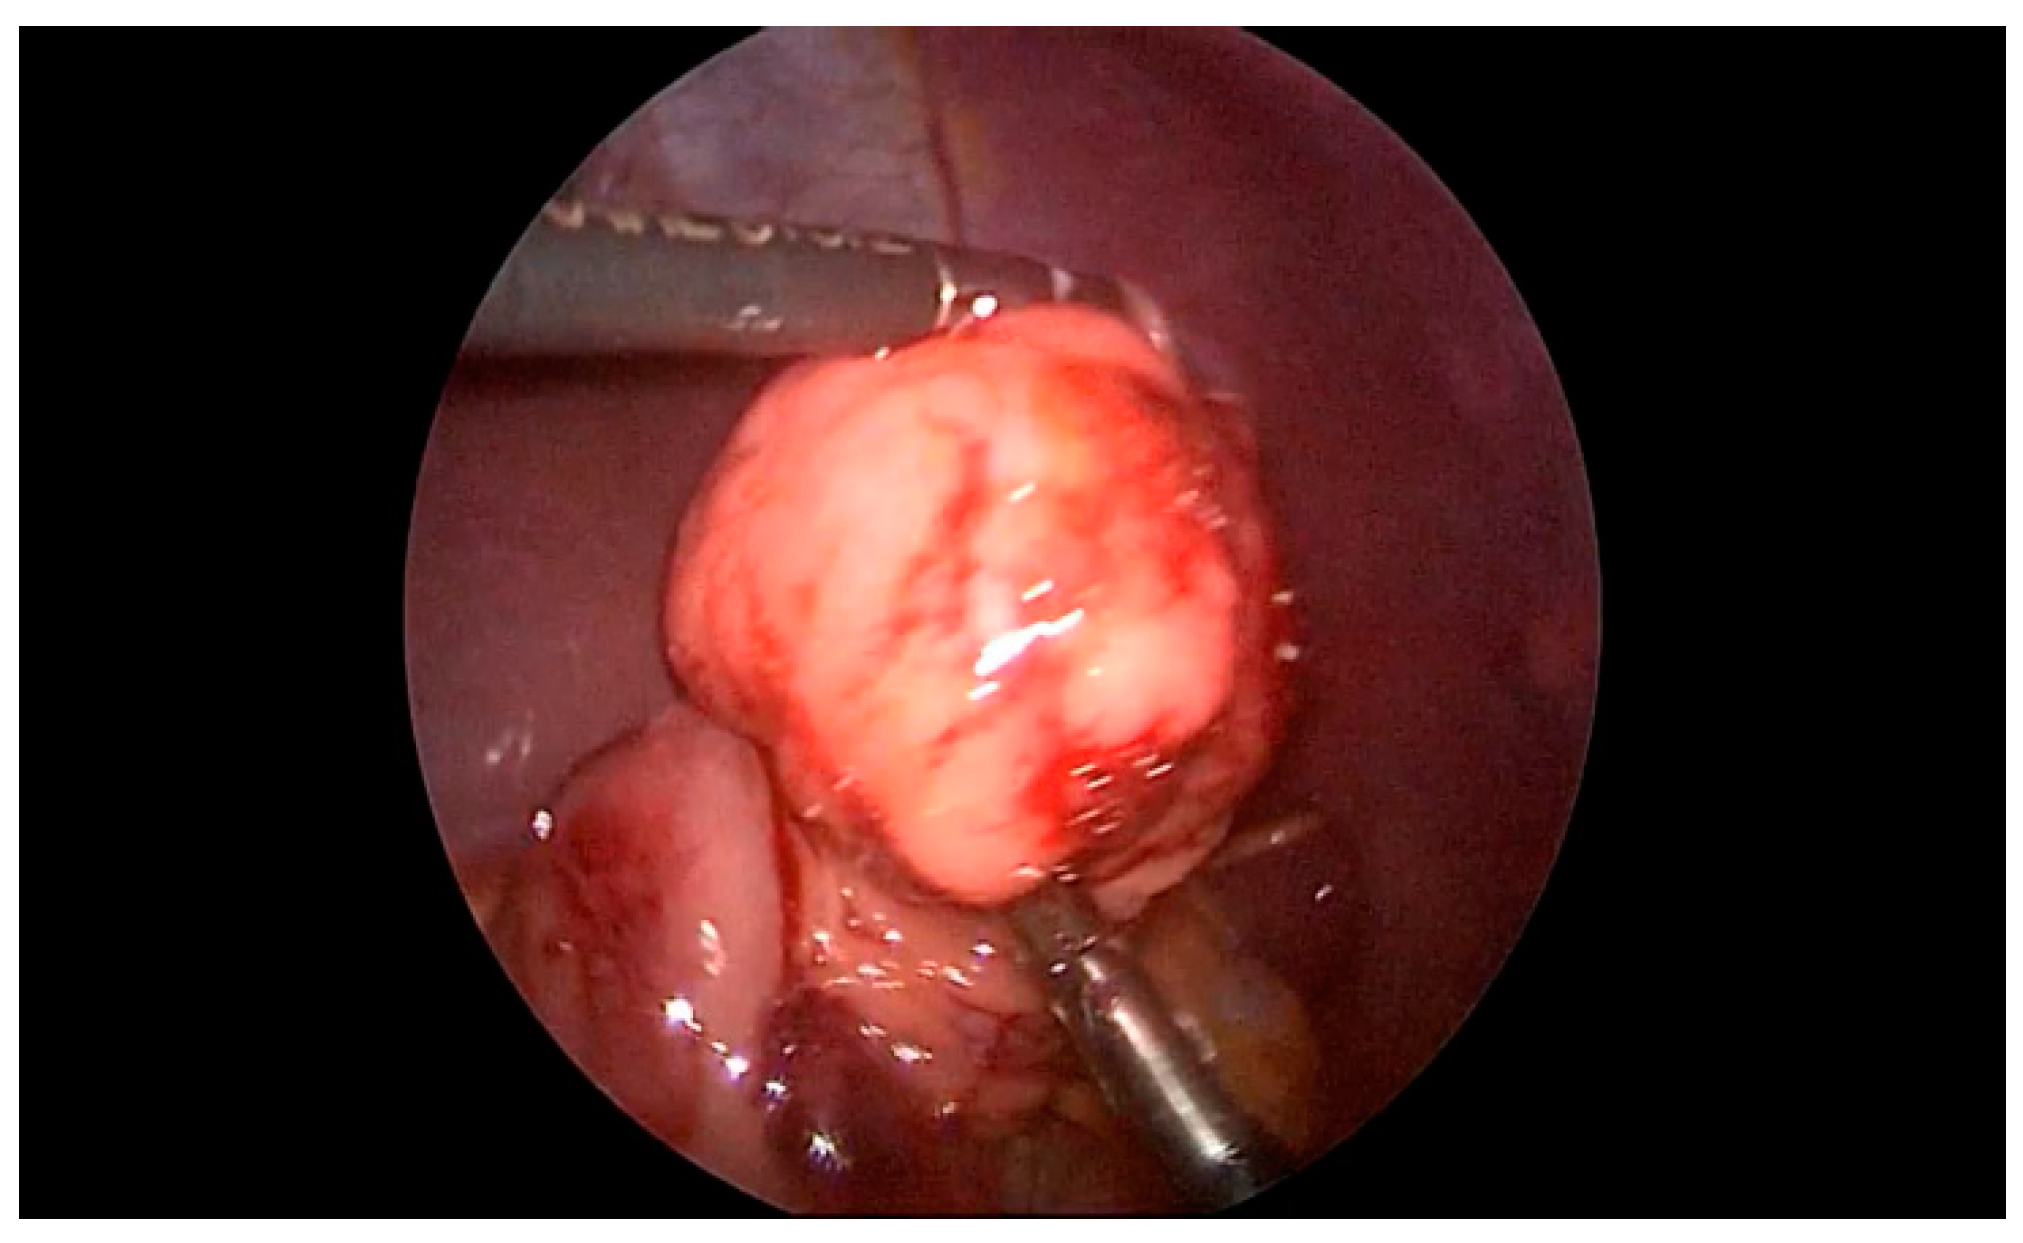

The seventh case in our case series is a 6-year-old boy who was referred to our clinic for a suspected ileocecal invagination. A hydrostatic desinvagination guided by ultrasound was attempted, and a patent ileocecal valve was confirmed. A pseudo kidney formation remained, indicating the possibility of an invagination of the duodenum and small intestine. A repeated ultrasound demonstrated that a pseudo-invagination was still present in the upper left quadrant. An MR-enterography was performed and demonstrated a 20-centimeter long suspected intussusception in the left hemiabdomen beginning in the third part of the duodenum and continued below the ligament of Treitz. Multiple polyps of the duodenum and jejunum were suggestive of Peutz–Jeghers syndrome as well. The most proximal polyp with a diameter of 6 cm produced a marked narrowing of the distal part of the duodenum and proximal jejunum. An esophago-gastro-duodenoscopy was performed, and a biopsy was taken. The biopsy confirmed the presence of a hyperplastic polyp of the duodenum. Then, the duodenum and jejunum were exposed using a combined laparoscopic–endoscopic “rendezvous” procedure (Figure 3A). A vertical incision was made on the highest position of the jejunal wall, and the mucosa was mobilized. However, the polyp could not be visualized during the first attempt. Then, we decided to use a partial Cattell–Braasch maneuver and resection of the ligament of Treitz for better mobilization of the duodenal mucosa (Figure 3B). After the resection of the ligament, the natural curvature of the duodeno-jejunal flexure was straightened. The straightened duodeno-jejunal junction allowed for the visualization and resection of the duodenal polyp (Figure 4). A second enterotomy was performed distally on the jejunum as well and two more polyps were resected (diameter 20 and 15 mm, respectively). The histology confirmed Peutz–Jeghers syndrome.

Figure 4.

Laparoscopic excision of the duodenal polyp (The straightened duodeno-jejunal junction allowed for the visualization and resection of the duodenal polyp during repeated mucosal mobilization).

For decades after minimally invasive laparoscopic surgery has been introduced, duodenal lesions were impossible to resect using this approach. Recently, more and more surgeons are attempting to extend their field of work to the duodenum and endoscopic guidance can be of tremendous help during this procedure. Here, we reported a case of a duodenal polyp treated in this way. The Cattell–Braasch maneuver and resection of the ligament of Treitz were used in order to straighten the natural duodeno-jejunal flexure. In 1960, Cattel and Braasch described the technique for the mobilization of the third and fourth portion of the duodenum that is used until today [16]. This maneuver consists of dissection of the line of Toldt from the common bile duct until the ligament of Treitz. Additional mobilization of the suspensory muscle of the duodenum (ligament of Treitz) was performed in the case we report here for complete mobilization of the duodenum. After the resection of the ligament, the natural curvature of the duodeno-jejunal flexure was straightened. The straightened duodeno-jejunal junction allowed for the visualization and resection of the duodenal polyp during repeated mucosal mobilization. Nowadays, laparoscopic endoscopic cooperative surgery, combining endoscopic submucosal dissection and laparoscopic seromuscular incision, is reported to be successful in treating duodenal lesions as well [17].